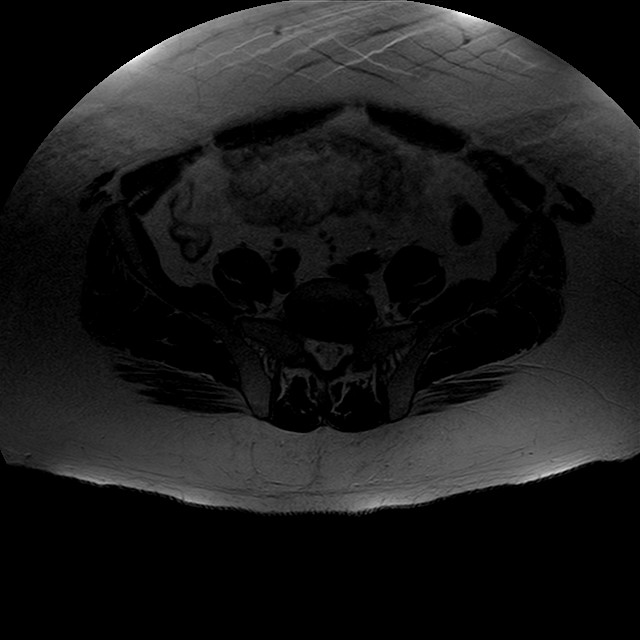

Esami: RMN BACINO

eT2w TSE

Evidenti e simmetriche alterazioni osteofitosiche in regione coxo femorale con riduzione delle rime articolari. Degenerazione completa del cercine glenoideo. Non attuali segni di versamento articolare. Non segni di edema osseo che escludono attuale algodistrofia od osteonecrosi. Lieve e simmetrica riduzione del trofismo della muscolatura glutea.